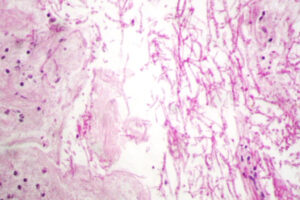

Corte de piel del párpado donde se reconocen epidermis y dermis, esta última con anexos pilosebáceos (GS) y cambios de dermatitis granulomatosa supurativa y crónica. El granuloma está mal formado

La candidiasis cutánea es típicamente una infección superficial que afecta principalmente la epidermis, aunque en casos de inmunosupresión o candidiasis mucocutánea crónica, la afectación puede ser más profunda. El hallazgo